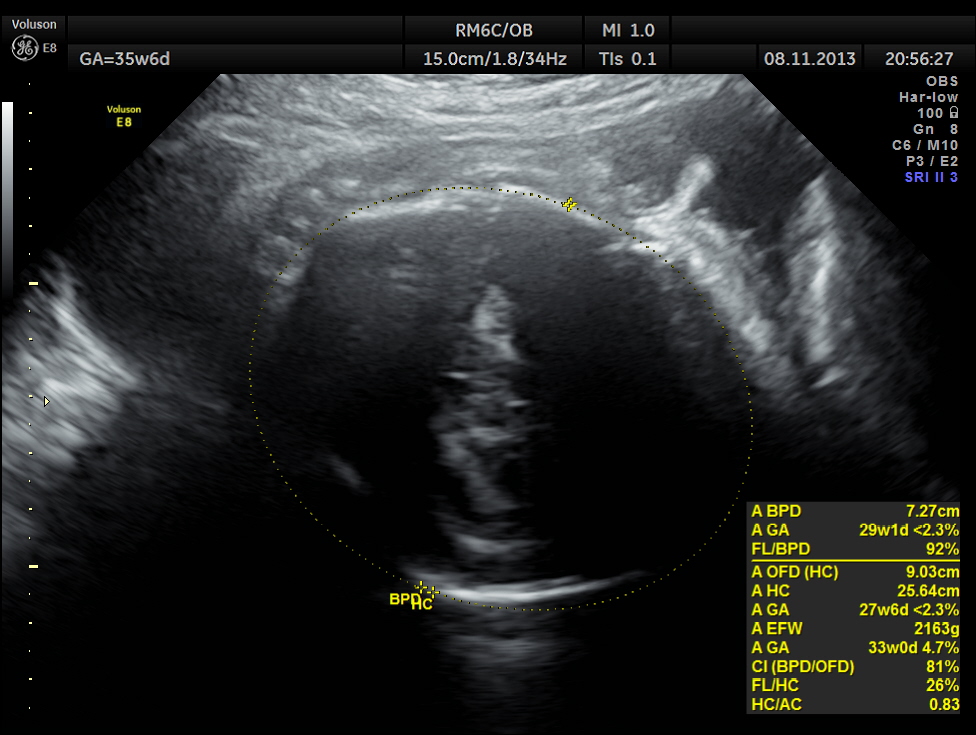

The scan was repeated at 36 weeks of gestation.

BPD, HC show < 2.3 % tile.

AC and FL appear to be normal.